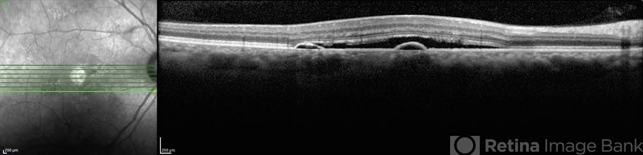

- central serous retinopathy (CSR), optical coherence tomography (OCT), pigment epithelial detachment (PED), central serous chorioretinopathy (CSCR), serous retinal detachment

- 62-year-old male patient with chronic central serous chorioretinopathy in his right eye. OCT shows serous neurosensory retinal detachment and retinal pigment epithelial detachment.